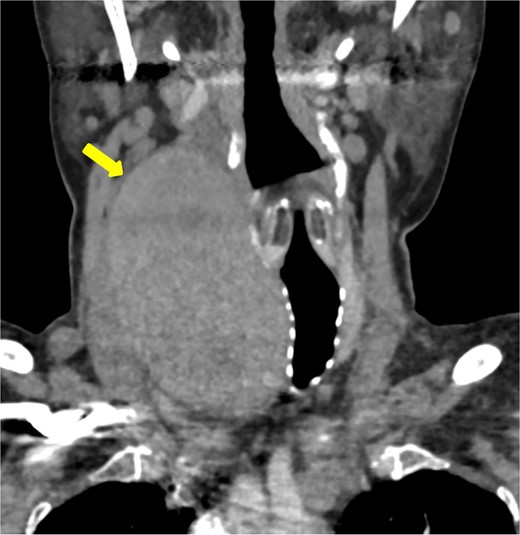

This case study describes a 76-year-old female with a history of type 2 diabetes and hypertension for fifteen years, controlled by her medication. She was swimming when she noted a sudden swelling in her neck. She presented to the emergency department of our hospital with right neck swelling for one-day duration. Physical examination shows a vitally stable patient with a localized neck mass not movable with swallowing and not associated with compressive symptoms. Computed tomography (CT) scan showed significant enlargement of the right thyroid lobe with heterogeneous predominantly hyperdense mass with mass effect on the airway with leftward deviation of the trachea (Fig. 1). Pre-operative CT Angiography showed active extravasation (Fig. 2). Also, there is a suspected right thyroid artery arching over the hematoma. The appearance of the artery raised the possibility of this artery being the cause of the hematoma. Then, a diagnostic angiogram was performed, which showed a dilated, ectatic-looking superior thyroid artery with flow into the hematoma, confirming the source of the hematoma. The patient successfully underwent angioembolization and hematoma evacuation without complications. During the procedure, an unexpectedly large solid component resembling thyroid tissue and a sac surrounding the hematoma were found. The patient was admitted to the Surgical Intensive Care Unit for post-operative monitoring and to prevent potential airway obstruction. The resected specimen was sent for further evaluation by pathology. Gross examination shows large dark brown hemorrhagic mass with thyroid tissue identified measuring 7.5 cm × 0.5 cm. Histopathology examination of the specimen revealed thyroid tissue with extensive hemorrhage and irregular dilated vascular spaces, as well as capillary-like vessels present in thyroid parenchymal tissue. Few thick-walled blood vessels were seen. These vascular channels are lined by bland endothelial cells (Fig. 3A, B). No cellular atypia, mitosis or solid growth pattern was observed. The vascular lining is diffusely positive for CD34, CD31, D2–40, and FLI1 (Fig. 3C, D). Given the above features of histopathology and immunohistochemistry studies, the diagnosis was compatible with primary thyroid hemangioma. Five months post-surgical resection, the patient’s follow-up indicates that she is in good health with no neck swelling, hoarseness of voice, or difficulty tolerating a regular diet. Her wound has healed without any signs of infection.

Coronal imaging of the unenhanced CT shows a large right thyroid lobe heterogeneous mass measuring 9.2 cm × 5.2 cm × 5.5 cm with mass effect on the airway and tracheal displacement to the left.